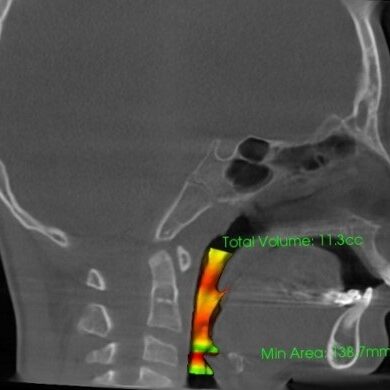

気道容積:治療前7.1 cc

気道容積:治療中11.3cc